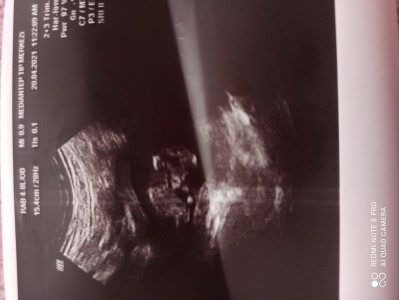

Cinsiyet tahmini yardim

11+5 gebelik

Ay bu hic anlasilmiyor. Benim 11+3 luk ultraayonunda herseyi girunurdu. Sekli belliydi yani

Kafayı öne eğmiş dedi doktorum

Ha simdi oldu. Kiz sanki

Kiz bnce cnmmm hayirliisi olsun insaallah

Bence kiz sanki öyle gordum